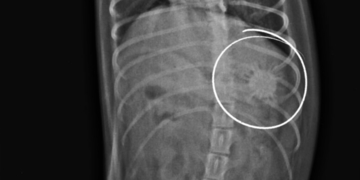

Неожиданные находки внутри наших пациентов

...или когда важно вовремя обратиться к врачу